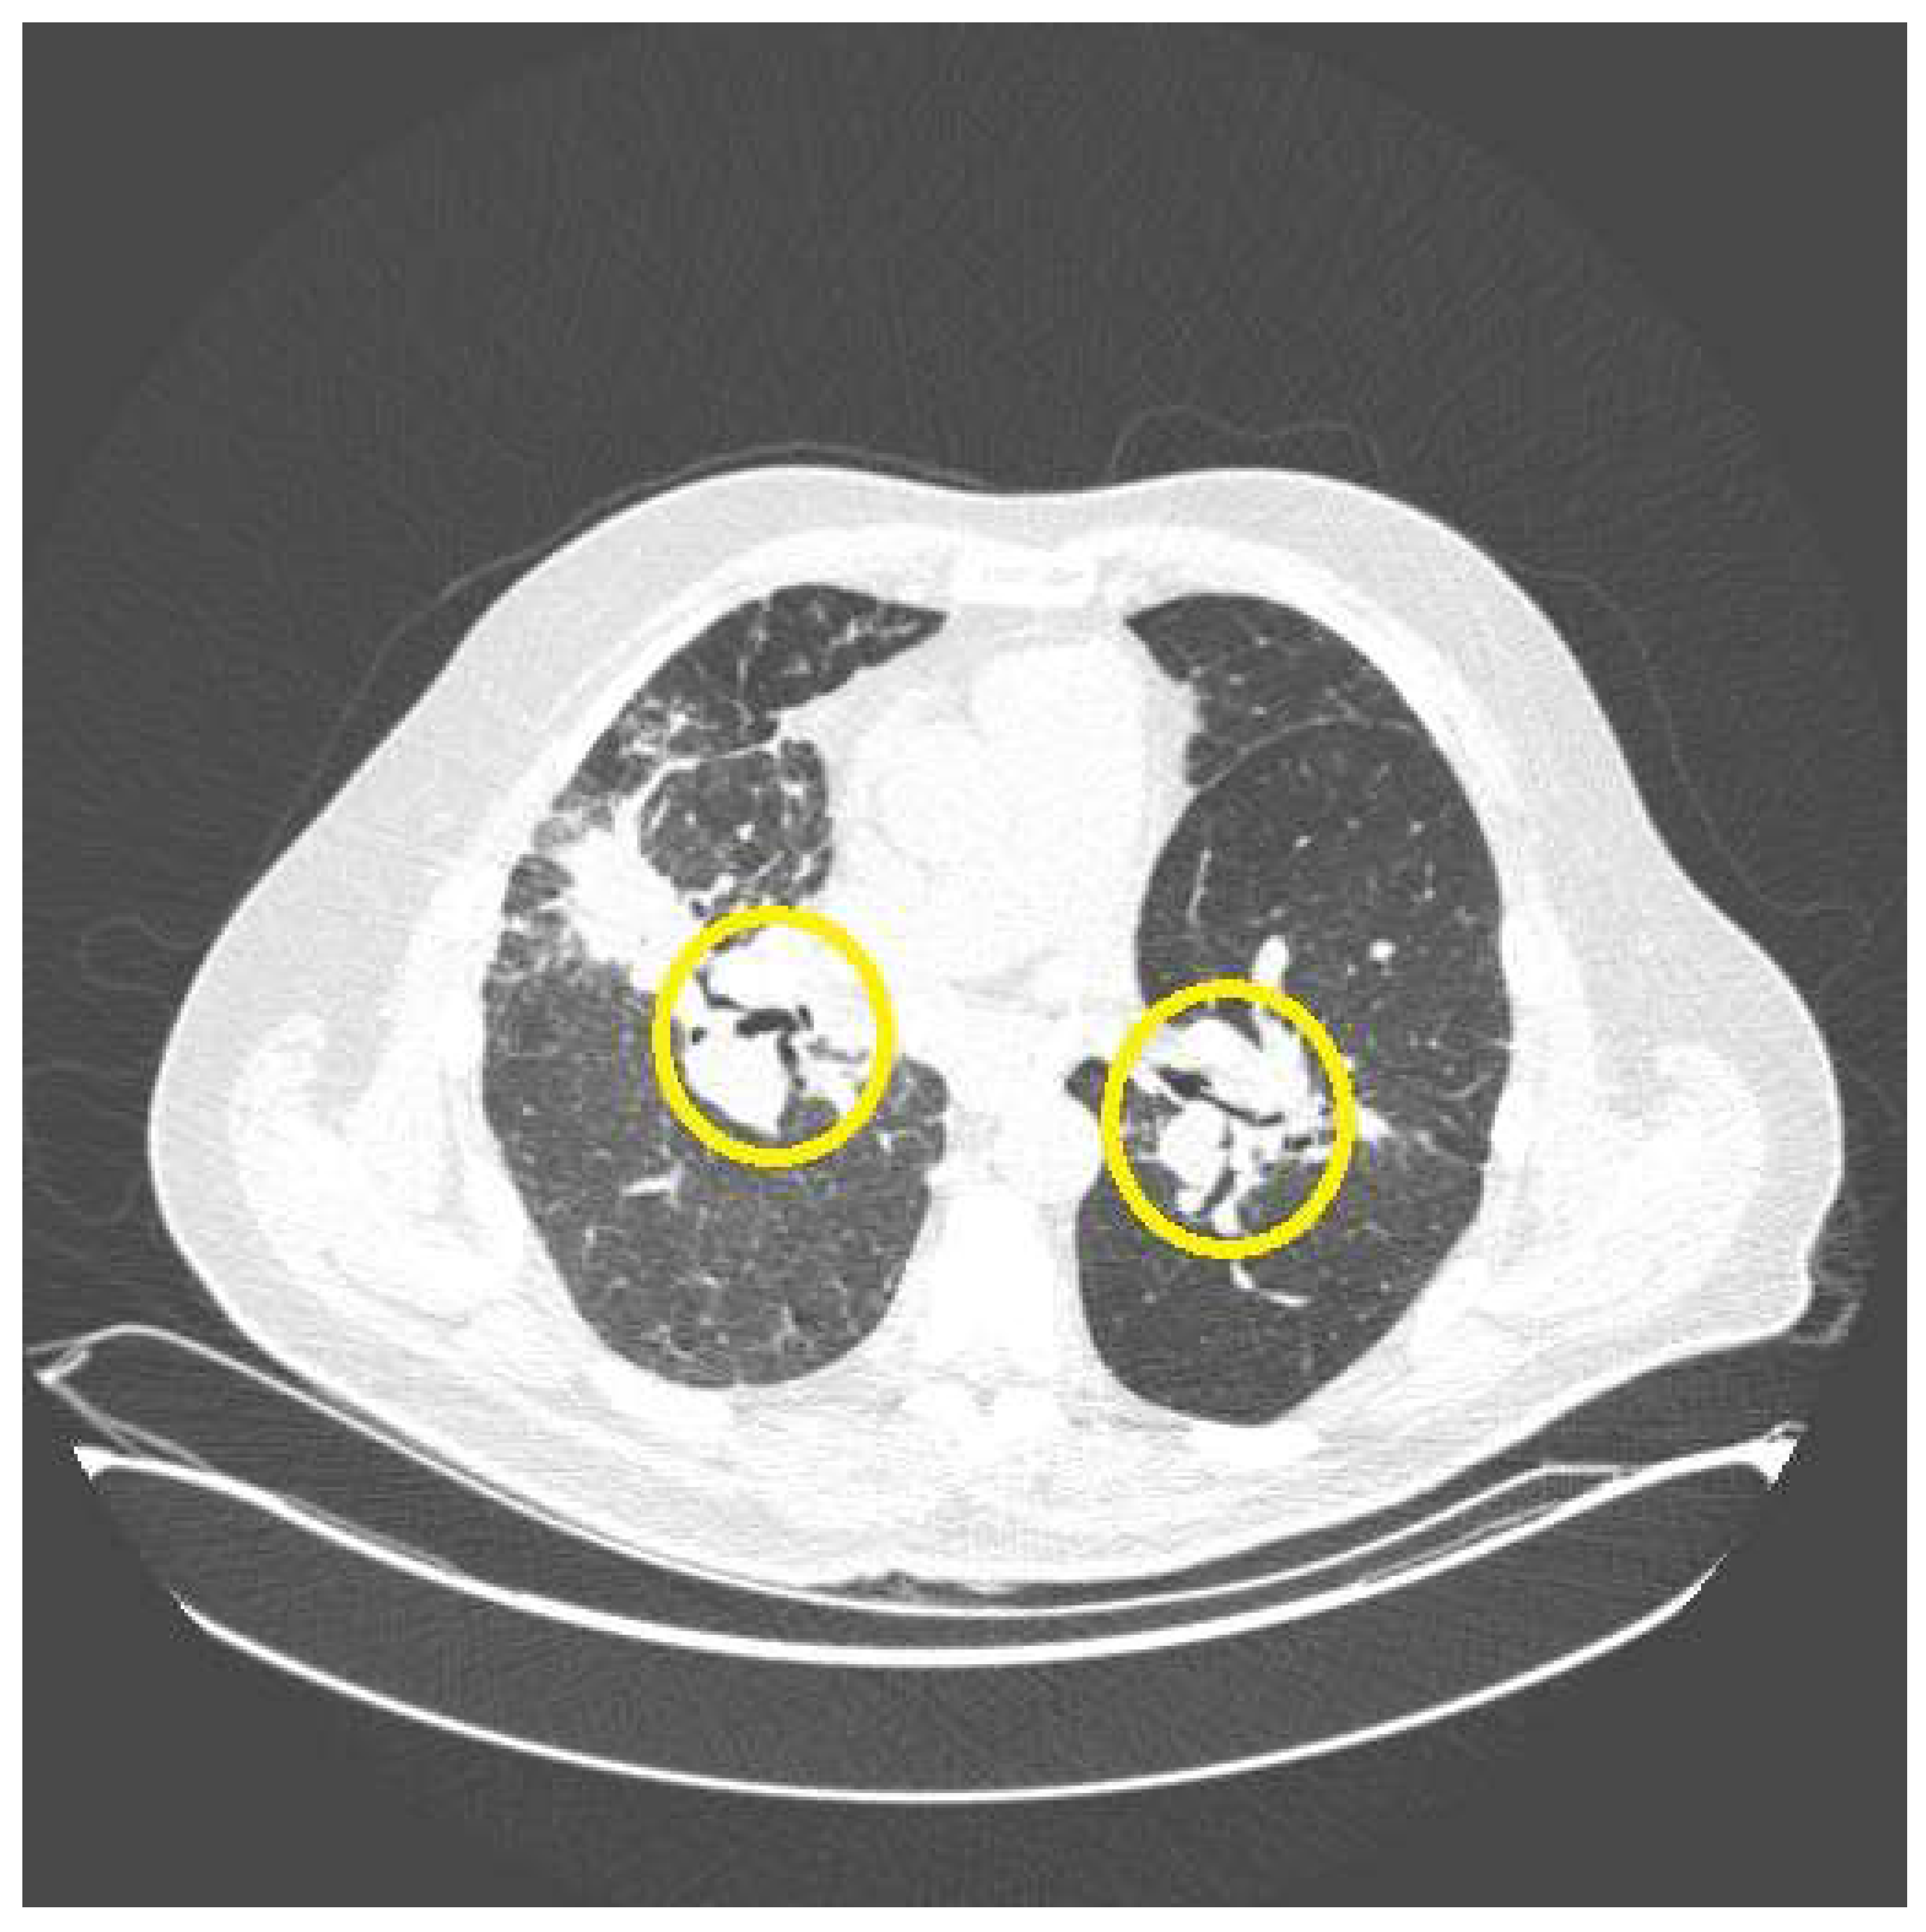

| Bronchiectasis | Fibrocystic sarcoidosis | Bronchiectasis from airway fibrosis from previous granulomatous inflammation. Hemoptysis from infectious bronchitis/bronchiectasis |

| Aspergilloma/Chronic aspergillus lung infection | Fibrocystic sarcoidosis | Aspergillus colonization of devitalized lung with subsequent locally invasive disease |